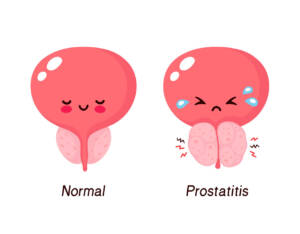

Nell’Urologia: in caso di ipertrofia e iperplasia prostatica.

- dell’ipertrofia prostatica benigna